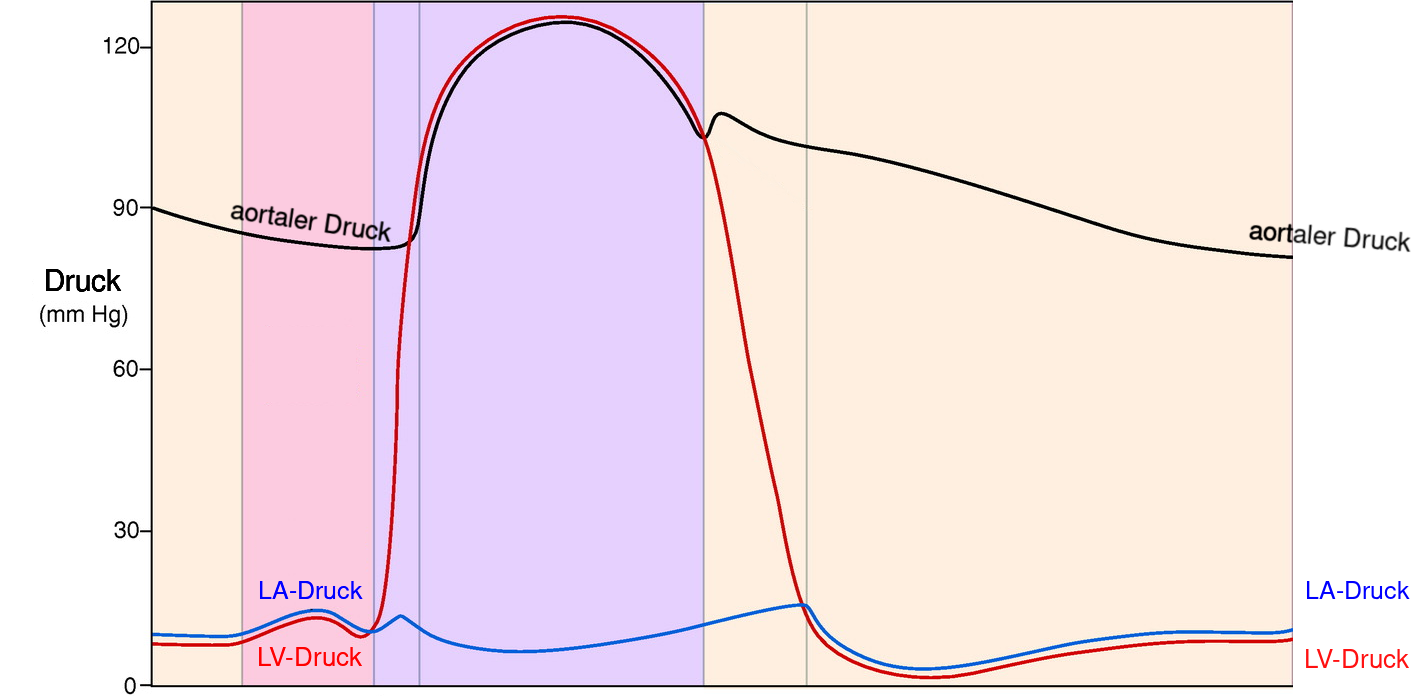

2 Phasen Herzaktion

- der ventrikulären Systole ist die atriale Systole vorgelagert

Vorhofkontraktion (atriale Systole)

- aktive linksventrikulären Füllung

- trägt zu 20 bis 30 Prozent zum gesamten linksventrikulären Füllungsvolumen bei

- erhöht normalerweise den diastolischen Druck hierdurch um weniger als 5 mmHg

die ventrikuläre Systole (kardialer Output)

- durch die Kontraktion hervorgerufene Inwärtsbewegung der Herzmuskelwand steigt der Druck in der Herzkammer —

- wenn der Druck in den Herzkammern den Druck in der Aorta übersteigt, wird Blut ausgeworfen —

die ventrikuläre Diastole (kardialer Input)

- entscheidend für die linksventrikuläre Füllung und damit der Herzfunktion

- für die Füllung muss der LV-Druck kleiner als der LA-Druck sein

- diastolischer LV-Druck wird bestimmt durch intraventrikuläres Blutvolumen, ventrikuläre Dehnbarkeit (Compliance) und durch den von Herzbeutel und rechter Herzkammer auf den linken Ventrikel ausgeübten externen Druck

1. Phase Diastole: isovolumetrische Relaxation

- Zeitraum zwischen Aortenklappenschluss und der Mitralklappenöffnung

- Druck im linken Herzen nimmt bei gleichbleibendem Volumen ab

- rascher Druckabfall

- Aufdrehen (Untwist) und elastische Rückfederung (Recoil) des linken Ventrikels ➙ Saugeffekt ➙ Mitralklappenöffnung und Ventrikelfüllung führt

2. Phase Diastole: auxotonische Relaxation

- Zeitraum zwischen Mitralklappenöffnung und atrialer Kontraktion

- mit Mitralklappenöffnung füllt linker Ventrikel mit variablen Druck

- in späterer Phase Entspannung sämtlicher Herzmuskelzellen

- linke Ventrikel nun nachgiebig, leicht dehnbar und weist normalerweise nur minimalem Widerstand gegenüber Füllung auf